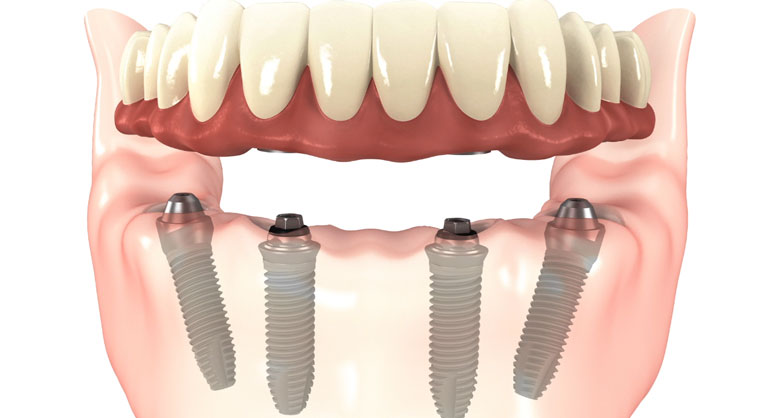

3. All-on-4 and  All-on-6

A full fixed bridges anchored to dental implants is an ideal and permanent solution for edentulous jaw. It is stable and provides high esthetics. It feels similar to having a new set of teeth again. Full implant bridges is however relatively costly and will need good bone condition for placement in each area.

All-on-4/ All-on-6 and zygoma implants are immediate function and graftless solution implants. The implant concept tilts posterior implants to maximum jaw bone volume on the anterior area. Where there is insufficient bone, long zygomatic implants may be placed to hold a fixed hybrid denture in place.